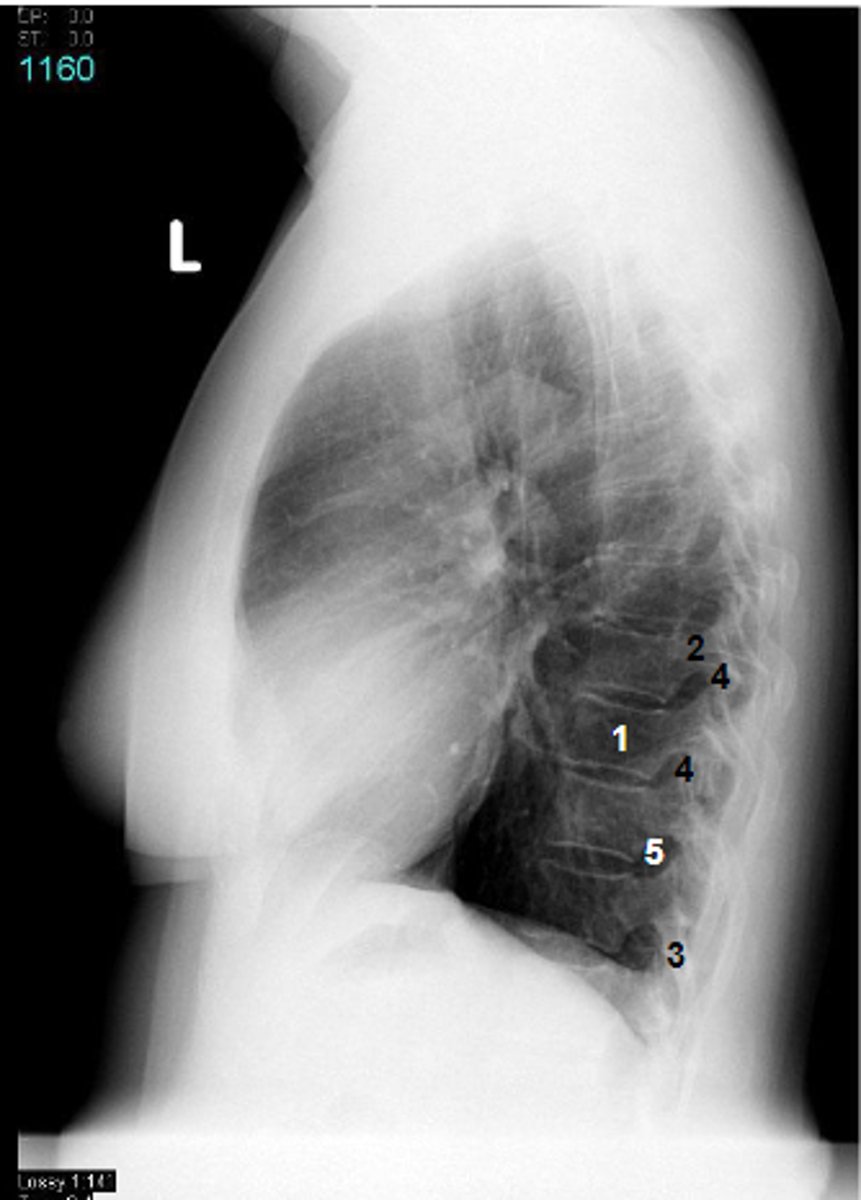

1

at what number is the body

2

at what number is the pedicle

3

at what number is the spinous process

4

at what number is the articular process

5

at what number is the intervertebral foramen